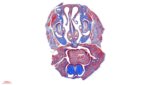

Luxol_Mouse-Brain__20250214105026_viewcapture-4